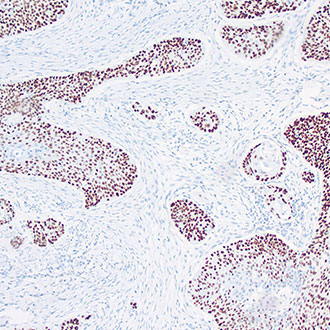

MLH1

MLH1 -